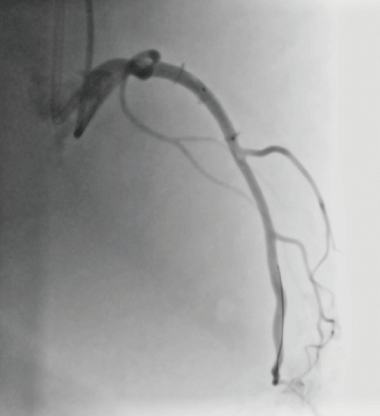

X線透視下で慢性完全閉塞病変(Chronic Total Occlusion)に対する経皮的冠動脈形成術(PCI)のシミュレーションが可能です。左冠動脈と右冠動脈をつなぐ側副血行路を有し、antegrade approachとretrograde approach双方のアプローチが可能です。

標準モデルには、LAD、LCX、RCAそれぞれの近位部に1か所ずつ病変部を作成してあります。側副血行路は、Type1はapex、AV grooveのルート、Type2はこれらに加えseptal branchのルートが用意されています。取り替え式の冠動脈パーツの位置を変えることで、閉塞⾎管を選択することができます。例えば、RCA近位部にCTOの病変パーツをセットしておき、RCA側からantegrade approachを試み、続いてLAD側からのretrograde approachをトライするといったシナリオが可能です。

心拍数を30~120bpmの間で調整でき心臓モデル(冠動脈を含む)の拍動と循環を実現します。臨床の造影に近い画像を再現できます。